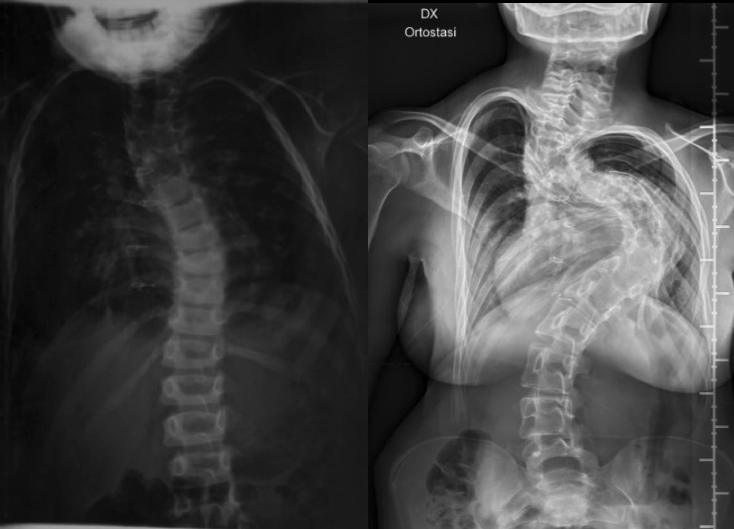

Anche Vincenzo, un bambino di 5 anni, ha una diagnosi di sindrome di DiGeorge, e anche lui ha iniziato a presentare una scoliosi molto precoce, all’età di soli 4 anni. A differenza di Giada, Vincenzo è stato sottoposto precocemente a terapia chirurgica, con ottimi risultati sulla sua scoliosi, che risulta appena accennata all’ultima Rx di controllo (Figura 2).

Le storie parallele di Giada e di Vincenzo dimostrano efficacemente come, davanti a una scoliosi precoce in un contesto sindromico, la terapia chirurgica debba essere intrapresa il prima possibile. I loro nomi potrebbero essere sostituiti da quelli di tanti altri bambini con molte altre sindromi (Prader-Willi, neurofibromatosi, Marfan, Noonan ecc.), ma l’approccio terapeutico non deve essere diverso. Posticipare la chirurgia prediligendo una terapia conservativa comporta un’evoluzione del danno al rachide, aumentando la difficoltà dell’intervento e ovviamente peggiorandone l’outcome.